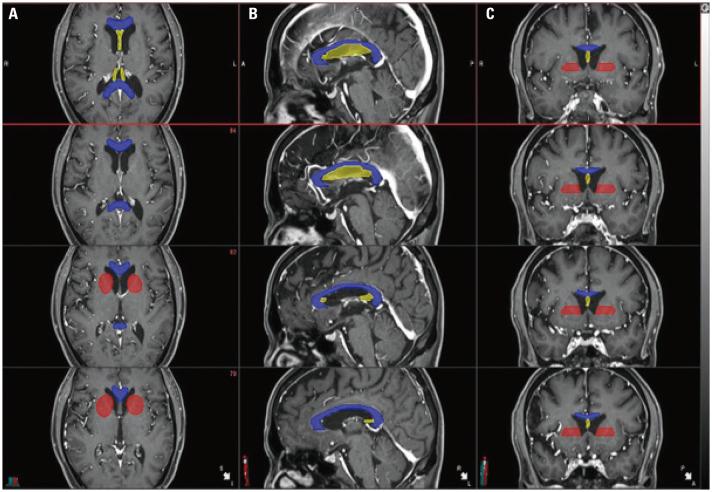

A total of 67 patients treated between 2009 and 2019 were analyzed. SRN was defined according to the following three criteria: 1) radiographic findings, 2) symptoms attributable to the lesion, and 3) treatment resulting in symptom improvement. Various contours, including the fornix, were delineated. Univariate and multivariate analyses of the relationship between RT dose and SRN, as well as receiver operating characteristic curve analysis for cut-off values, were performed.

分析了 2009 年至 2019 年间治疗的 67 例患者。根据以下三个标准定义 SRN:1)影像学发现,2)归因于病变的症状,3)治疗导致症状改善。对包括穹窿在内的各种轮廓进行了描绘。进行了 RT 剂量与 SRN 之间的单变量和多变量分析,以及截断值的受试者工作特征曲线分析。